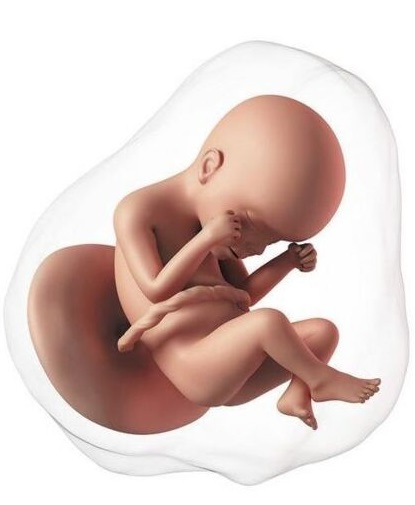

En esta semana inicia el segundo trimestre del embarazo. El feto mide aproximadamente 80 y 95 mm. El bebé crece rápidamente, los brazos alcanzan la proporción adecuada en relación al tamaño del cuerpo. La piel, que ya no es tan "transparente", se cubre aún más por vello denominado lanugo. Los músculos de la cara se desarrollan más, su sistema nervioso está más desarrollado, abre la boca en forma de bostezo, hasta se pueden meter los dedos en la boca. Al abrir la boca entra líquido amniótico, el cual pasa al estómago y los intestinos, lo cual permite que estos crezcan y se desarrollen.

En la semana 15 de gestación, el feto mide entre 10 y 11 cm. En lo referente a los huesos, siguen desarrollándose. Comienza el proceso de osificación porque retienen más calcio, pero aún son elásticos porque en su mayoría están constituidos por cartílago, lo que permite una relativa elasticidad de cara al parto.

Cada vez se parece más a un bebé. Mide aproximadamente 11 a 12 cm y pesa unos 80 gramos. La proporción cabeza-cuerpo se acerca más a la que tendrá después del nacimiento, las orejas y los ojos están casi en su posición final. Los brazos y las piernas se alargan. La conexión entre el cerebro y los músculos madura, el bebé empieza a realizar movimientos coordinados. Puede mover los ojos, tragar, abrir y cerrar las manos, flexionar las extremidades y también puede coger con las manos los pies e incluso el cordón umbilical. La función del riñón está completa, ahora la orina será el principal componente del líquido amniótico. Un nivel normal de líquido indica que el feto está orinando de manera adecuada.